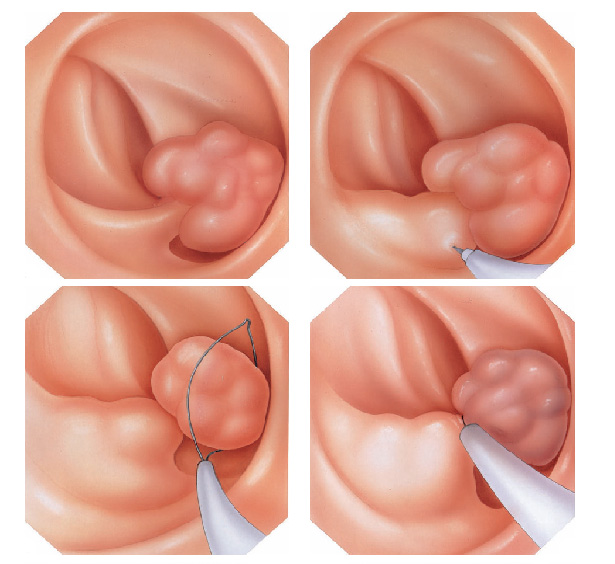

Mucosectomia é o procedimento realizado quando há necessidade de retirada de lesões maiores do trato gastrointestinal.

O exame de Mucosectomia é realizado através de injeção de liquido embaixo da lesão, através de uma agulha específica. Com isso a lesão se destaca das camadas mais profundas do intestino, diminuindo o risco de perfuração.

A retirada da lesão é feita com uma alça de polipectomia e o material é encaminhado para estudo anatomopatológico (no microscópio) da mesma forma que ocorre nas biópsias.

O que é a polipectomia?

A polipectomia é a remoção completa de um pólipo permitindo assim o diagnóstico exato e muitas vezes a cura do próprio problema. Existem várias técnicas para a realização do procedimento que dependem do tamanho e do tipo de pólipo a ser ressecado.

Polipectomia com alça diatérmica

Pólipos maiores necessitam ser removidos com alça e corrente de cauterização. Este procedimento permite cortar a base do pólipo e ao mesmo tempo coagular o local para evitar sangramentos.

Porém alguns pólipos possuem a base (pedículo) largo onde passam vasos calibrosos e por isto tem risco aumentado de sangramento na retirada mesmo usando a corrente de coagulação.

Nestes casos algumas medidas podem ser realizadas para diminuir o risco de sangramento:

Injeção de adrenalina na base do pólipo

Colocação de um laço na base do pólipo para estrangular o pedículo

Alguns pólipos não possuem a base alongada (pedículo), estes são chamados de pólipos sésseis. A remoção destes pólipos possui risco maior de perfuração do órgão pois como são planos ficam muito próximos da parede externa do órgão.

Mucosectomia

Para diminuir este risco, injeta-se com um uma agulha uma solução abaixo do pólipo para que ele levante e fique mais longe da parede do órgão. Após isto passa-se a alça diatérmica e realiza-se o

procedimento de polipectomia.